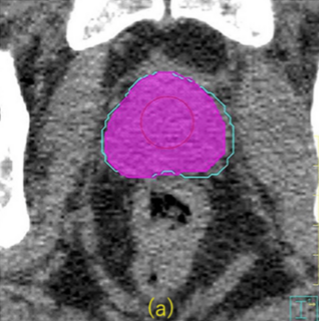

論文「Dosimetric Impact of Artificial Intelligence (AI)‑Based Autocontouring Software, OncoStudio, in High‑Risk Prostate Cancer Treatment Planning: A Three‑Group Comparative Study on the Slice Ranges of Seminal Vesicles」が発表されました。本研究では、OncoStudioによる高リスク前立腺がん患者の精嚢に対するAI自動輪郭抽出とマニュアル輪郭抽出との違いを線量で比較しています。CTV, PTVに対して、統計的に有意な線量差は認められず、処方に対する差は1%未満であることが示されました。この結果は、AI自動輪郭抽出が高リスク前立腺癌放射線治療計画において信頼性の高い選択肢であることを示唆しています。